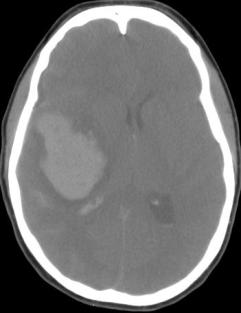

This is a slide from my first ct scan. I will do my best to explain what I learned about my ct scan.

A ct scan takes cross section images of the brain in layers. Doctors and Radiologists read these cross sections like a game of battleship to pinpoint the affected area and best course of action. This image is reversed. The left side of this image is actually the right side of the brain.

Note the following, when looking at this slide:

The skull bone is the white halo. At the “widow’s peak” of the skull bone, there is a fine white line(Midline Falx Cerebri) shifted towards the left.

2) The white cloud is located in the right side of the brain, the black butterfly looking thing is on the left side.

3) Apart from the skull bone, white in a brain ct scan is a bad thing. The white cloud is the blood clot. The white bumpy texture is blood in the subarachnoid space, (the space between the brain surface and the skull bone). In actuality, this subarachnoid area usually has a black bumpy texture, cerebrospinal fluid, the blood brain barrier. Blood in the brain is a toxic irritant and is BAD.

4) The black butterfly thing (frontal horns of the lateral ventricle) should be symmetrical and centered in the middle. Notice the butterfly is smushed and pushed towards the left.

Any way you looked at it, my CT scan was terrible.